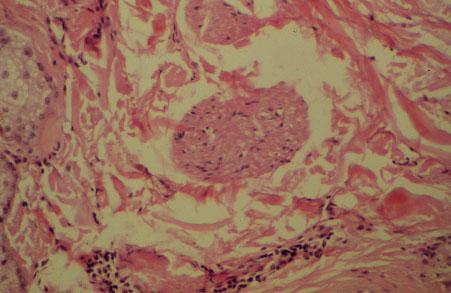

IX-57 (2) Slide 77, Scalp - Skin (H&E). High power view of a nerve bundle.